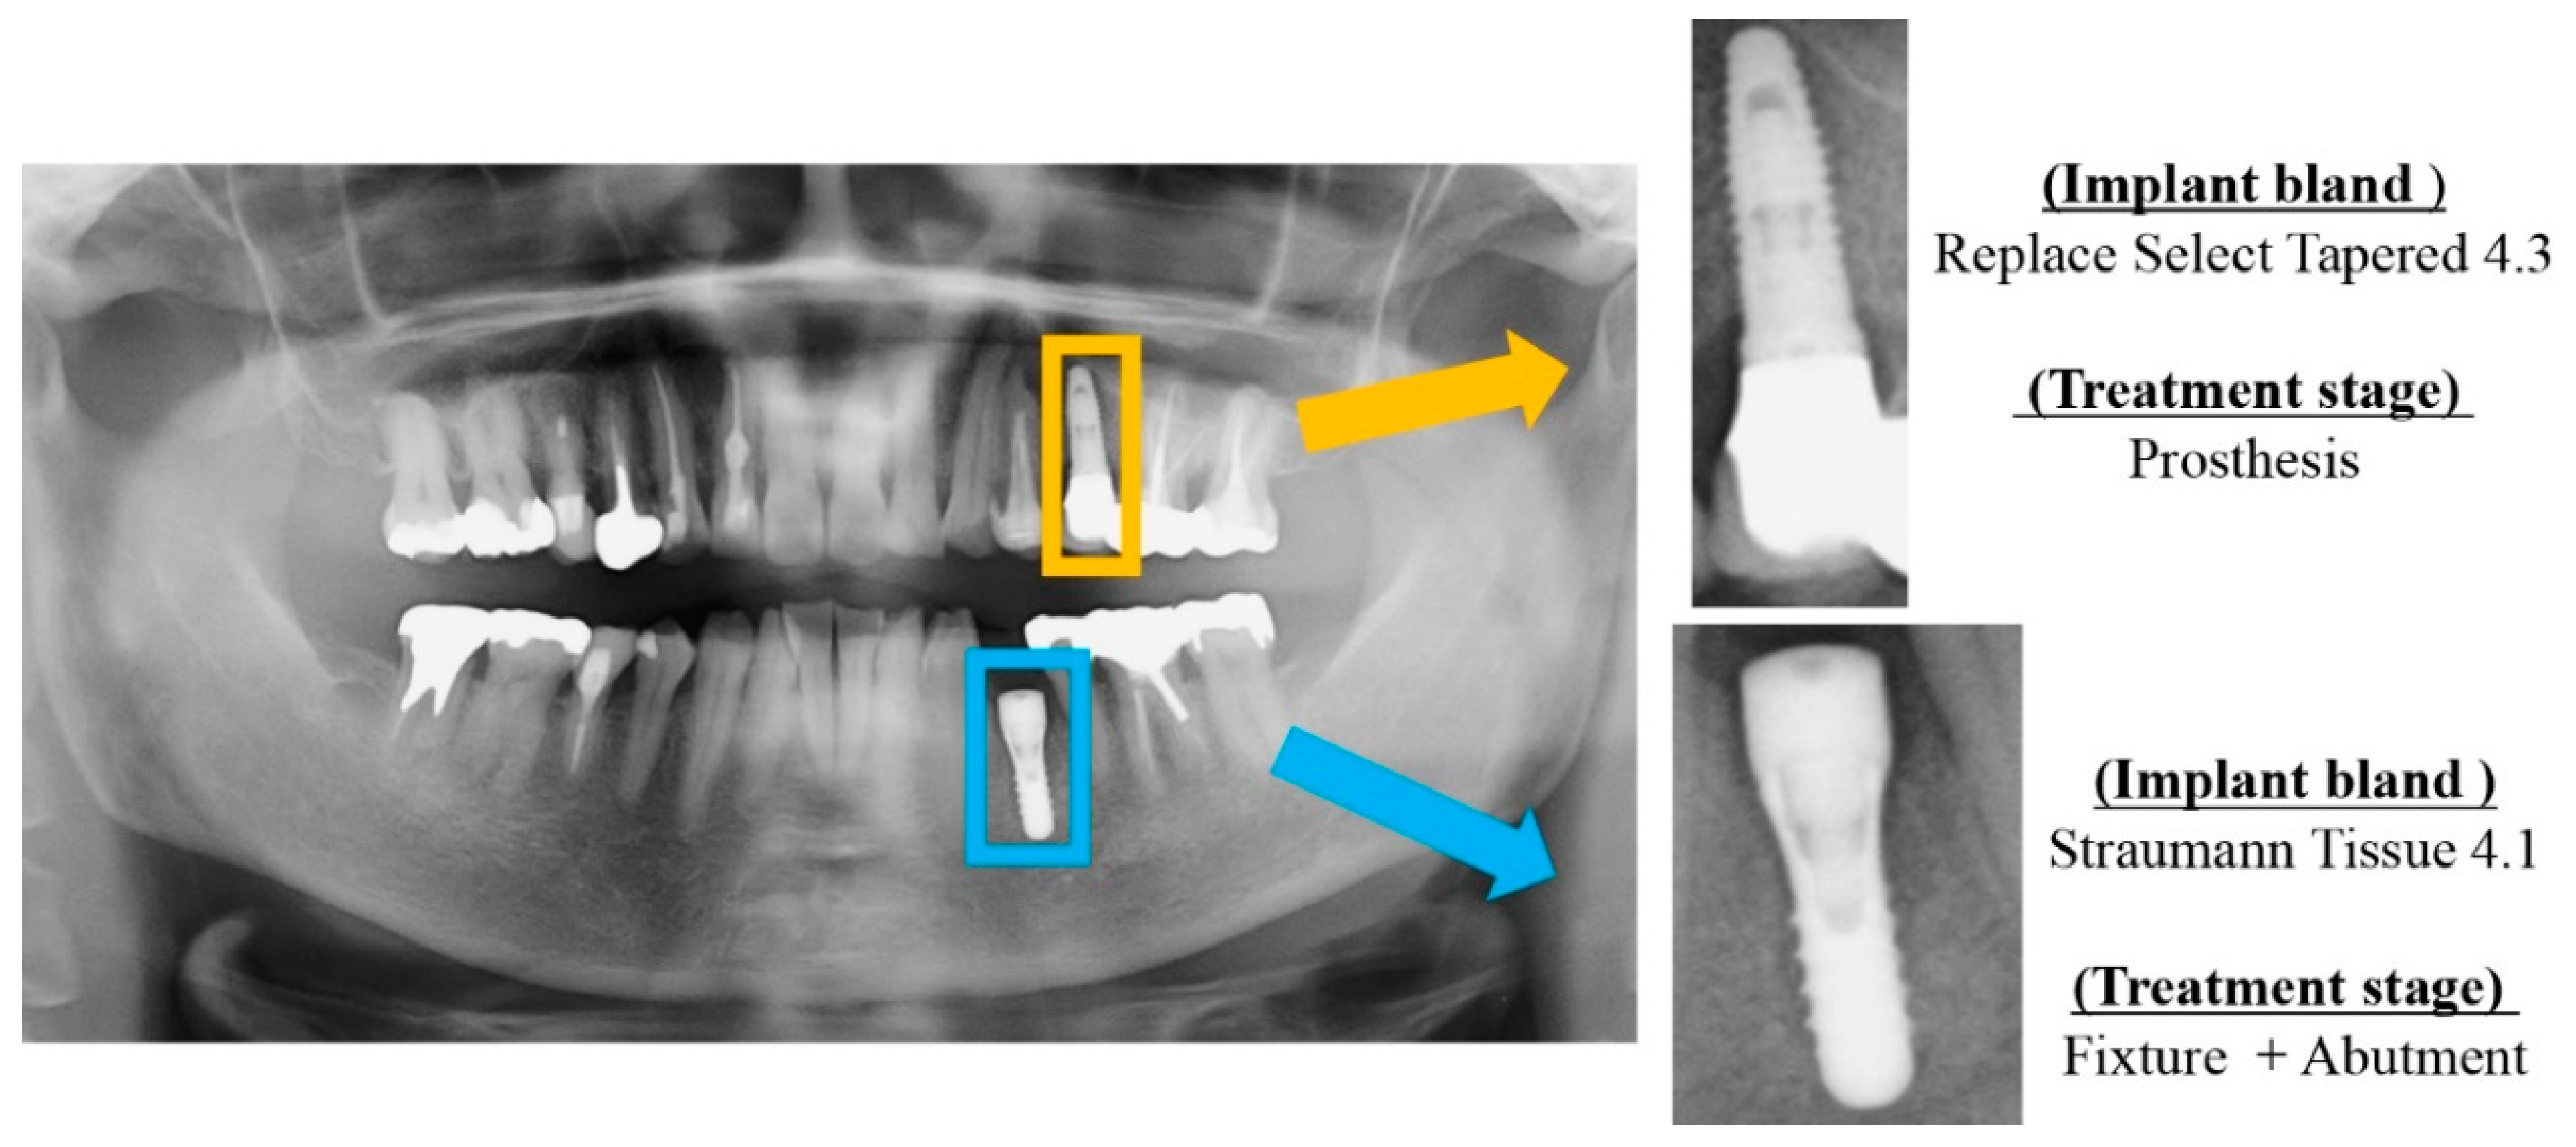

Each dental implant image included was manually cropped as needed for each dental panoramic radiograph taken. These dental implant data included implant fixtures, healing abutments, provisional settings, and final prostheses. For preparation before analysis, we used Photoshop Element (Adobe Systems, Inc., San Jose, CA, USA) to manipulate the images so that all dental implant fixtures would fit (see Figure 1 and Figure 2). The cropped image was saved in portable network graphics (PNG) format. Oral and maxillofacial surgeons who performed the cropping were completely unaware of the accurate implant brand of each patient.

Figure 1.

Cropping of dental implant imagery to include single fixtures. At the same time, the implant brand and treatment stage were labeled.

- Replace Select Tapered 4.3: Replace Select Tapered (Nobelbiocare, Göteborg, Sweden), diameter of 4.3 mm; lengths of 8, 10 and 11.5 mm.

- Straumann Tissue 4.1: Standard Plus Implant Tissue Level implants (Straumann Group, Basei, Switzerland), diameter of 4.1 mm; lengths of 8 and 10 mm.